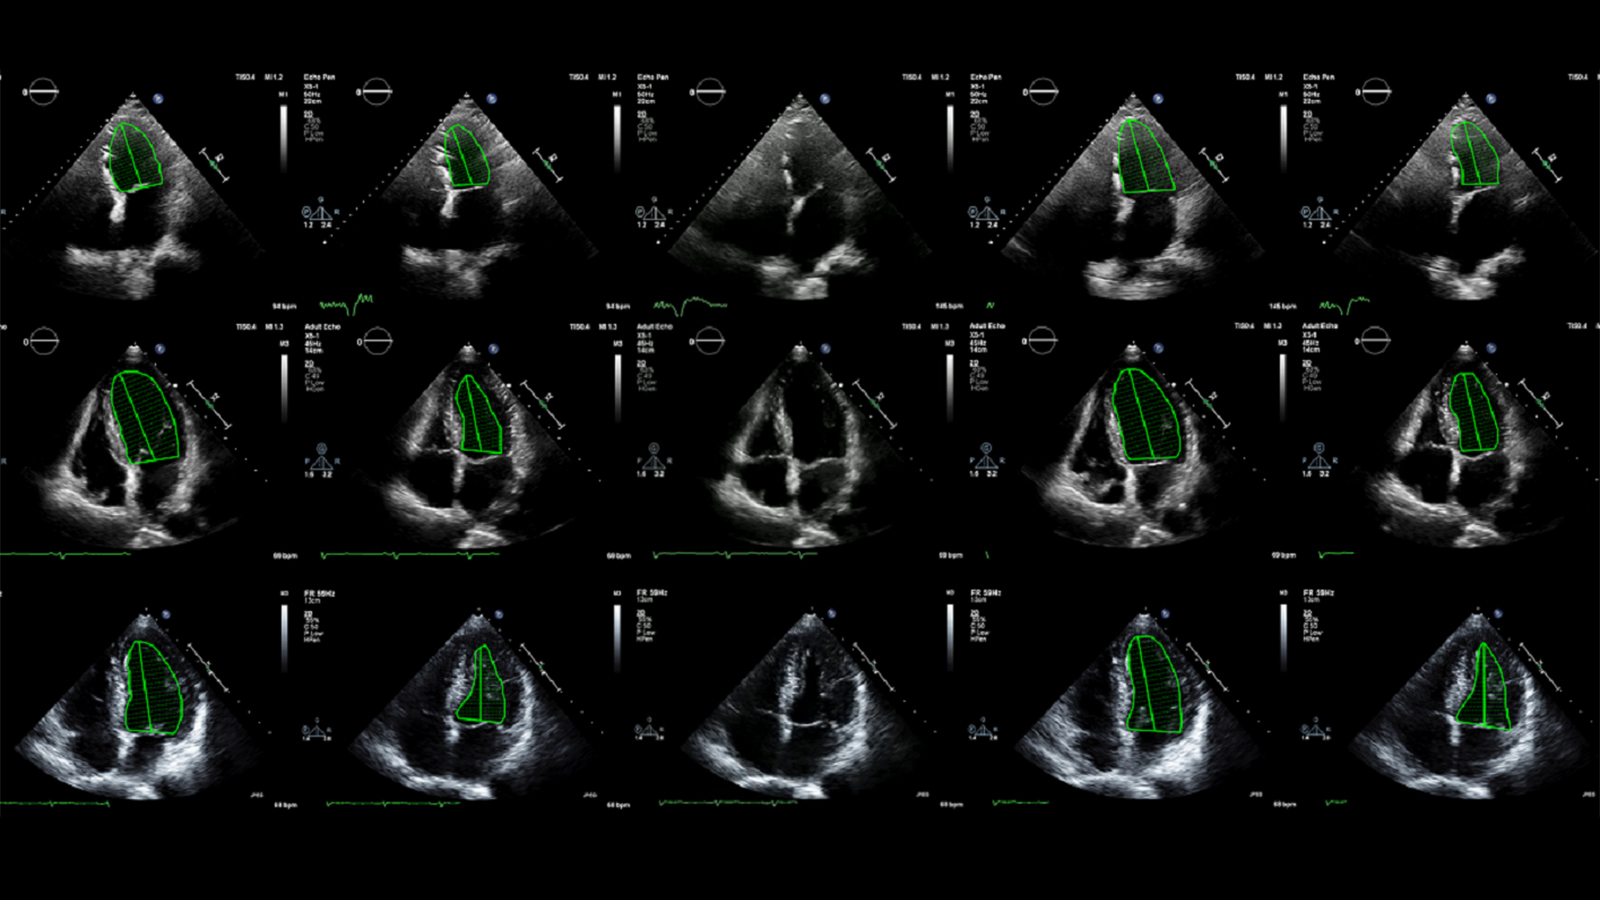

First-of-its-kind trial shows AI beat humans at analyzing heart scans

Echonet, an AI trained to assess a measure of heart function, has outperformed trained technicians in both accuracy and efficiency.